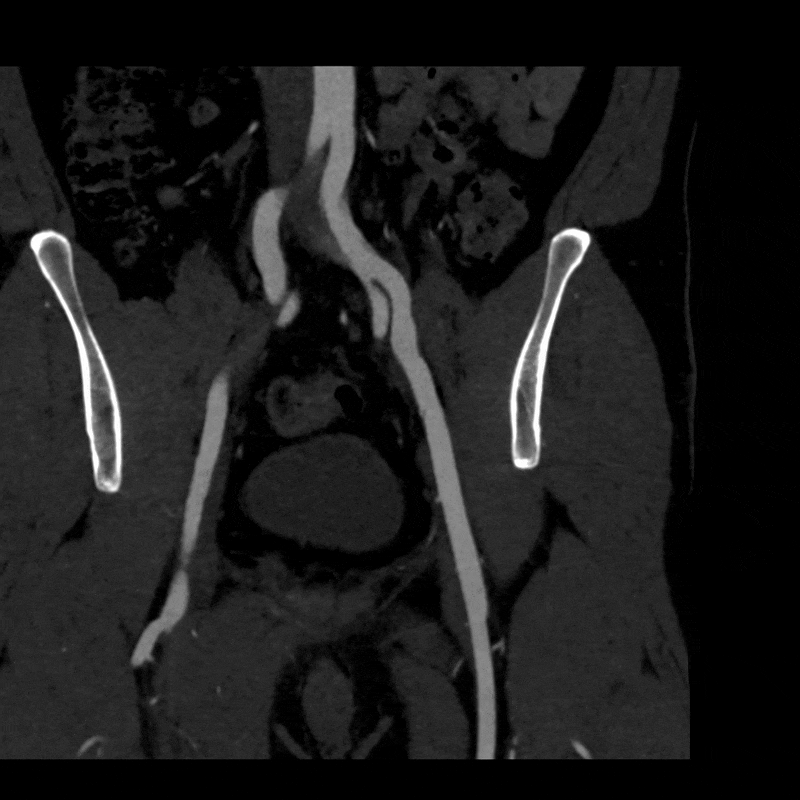

To better visualize the iliac anatomy, CPR loops were created to trace the artery along its course in both relaxed and stressed positions, allowing direct comparison of lumen size and curvature. VR views were generated with and without pelvic and femoral bone to show surrounding anatomical relationships. These complementary views help clarify how limb motion influences vessel shape and highlight narrowing that may be subtle or difficult to appreciate on axial slices alone. (Learn more about CPRs here, and VRs here).

Figure D: CPR of the left iliac artery in a relaxed position.

Figure E: CPR of the left iliac artery in a stressed position.

Figure F: CPR of the right iliac artery in a relaxed position.

Figure G: CPR of the right iliac artery in a stressed position.

When the patient moved into the stressed position, the right external iliac artery showed two areas of luminal narrowing (a temporary decrease in the size of the vessel’s opening). One narrowing was more proximal (closer to the vessel’s origin near the pelvis) at about ten to twenty percent, and the second was more distal (farther along the vessel toward the leg) at about thirty to forty percent. Both returned to a widely patent appearance (fully open) when the leg moved back to a relaxed position.

The left external iliac artery remained patent across positions, and the common iliac arteries were tortuous (naturally curving) without any fixed stenosis. This pattern aligns with external iliac endofibrosis, where motion causes the artery to change shape rather than a fixed obstruction, highlighting why positional imaging can reveal abnormalities that may not appear on routine resting studies.